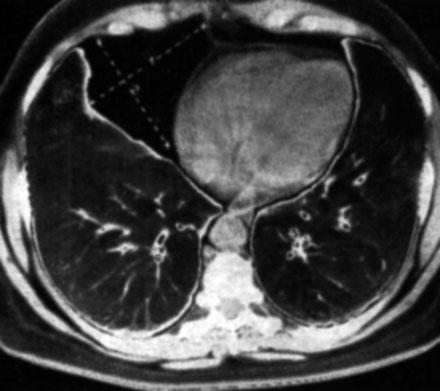

Пациент 75 лет поступил с клинической картиной правосторонеей пневмонии 20.02.12, по поводу чего лечился до 02.03.12 сейчас клиники пневмонии нет и готовят на выписку в удовлетворительном состоянии. А картина на контроле через две недели такая же. Возможно предположить наличие прямых или косвенных признаков центрального Neo правого легкого ?. Заранее спасибо!

ИМХО: справа в S3 было и сохраняется уплотнение лёгочной ткани перибронхиального харктера, которое с учётом клиники, можно раcценить как проявление пневмонии, которая в настоящий момент клинически разрешилась.Только вопрос какого характера пневмония -банальная или вторичная, параканкрозная остаётся открытым.Показана РКТ ( если недоступна, то как суррагат последней  срединная линейная томография, на проходимость бронхов) + бронхоскопия. Я бы ещё постарался поднять ФЛО-архив- не нравится низкое расположение малой междолевой плевры в медиальном отделе, за счёт чего это произошло?- уменьшение в объёме средней доли? ( если-да, то когда это возникло сейчас или давно?) или вздутие S3? Если ничего не сделают и выпишут пациента, то в случае варианта, что пневмония была на фоне нарушения проходимости бронха опухолевого генеза, следут ожидать скорого рецидива пневмонии.

Если посмотреть на боковую R-грамму лёгких от 20.02.12г, то нижние отделы занимает только тень диафрагмы, каких-то дополнительных образований в базальных отделах нет. На боковой R-грамме  от 2.03.12г.определяеся округлая тень( да и не одна), липома  за 10 дней вырасти не могла, скорее это тень нескольких скатов купола диафрагмы. Собственно говоря, сам факт наличия или отсутствия липомы не актуален, для пацента в 75 лет т.к. если она даже есть, это никак не моменяет тактику ведения пациента. Принципиальное значение имеет вопрос, что происходит с лёгкими и какой ожидать прогноз.

Просто, возможно я ошибаюсь, скорее врего ошибаюсь, но я не вижу на представленных изображениях ни скиалогических признаков пневмонии, ни скиалогических (прямых, или косвенных) признаков центрального рака.